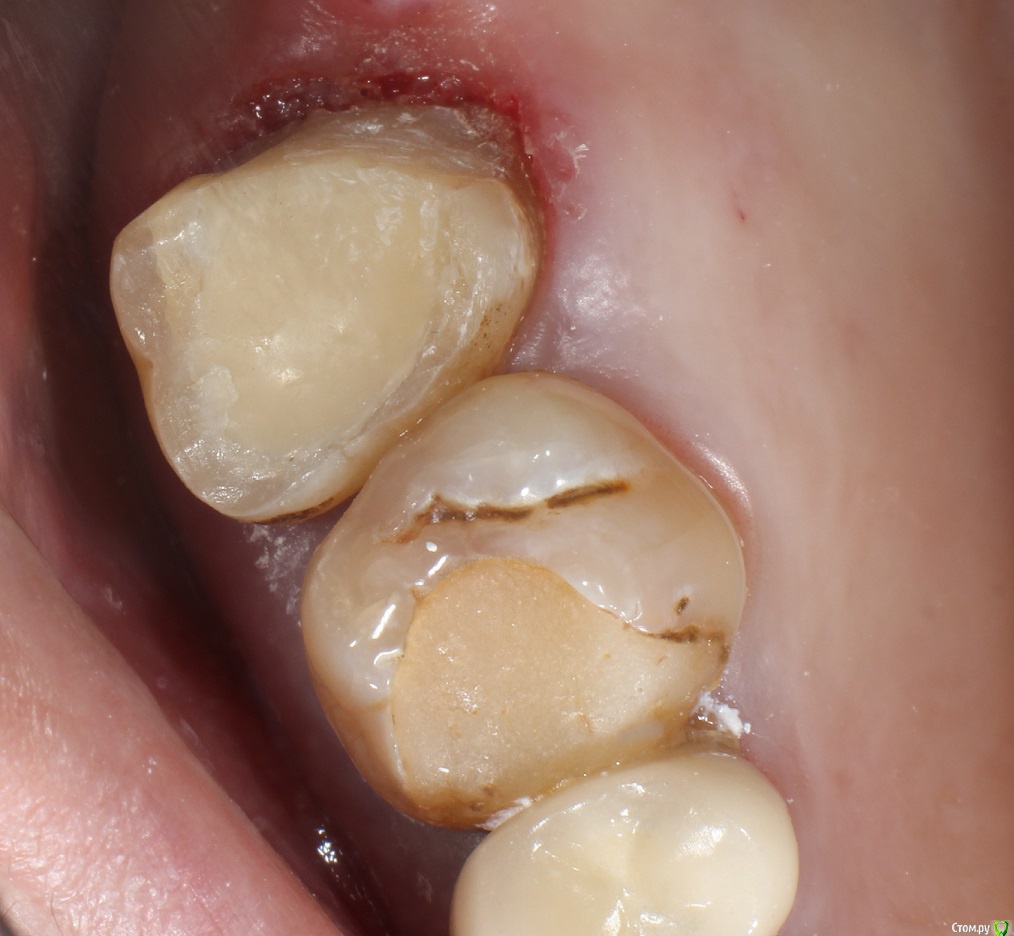

Кейс под названием: Что для тебя успешное эндо?

Пациент: девушка 16 лет. Задача дотянуть зуб сколько сможем по времени, затем имплантация.

Исходная ситуация:  симптоматический апикальный периодонтит. Отломок в медиально-щечном канале.IMG_20210716_134030.thumb.jpg.0b754f1cf44f10a3d2e05ed70884f5b7.jpg

Бился примерно 2 часа, Прошел медиально-язычный. Немного обошел обломок, за ним стопорюсь. Дистальный глухо. Оставил пульпосептин, готовился к удалению.

На следующем приеме жалоб нет, принял решение пломбировать что есть.

С пацом решили: если за 3 месяца не появится болей, и в прицельном не появится разряжение - то коронуем.

3 месяца спустя:

Устанавливаем коронку.

Прошло 1.5 года.

Звонит: ходуном ходит зуб. Думаю: ну, здравствуй, обострение, здравствуй, удаление. Пришла, оказывается расцементировка коронки. Делаем снимок: